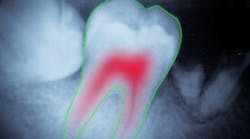

Root canals

One essential thing about root canal treatment is that it must be complete but not excessive. It is particularly important that endodontic treatment be accompanied by a detailed x-ray or CBCT examination of affected roots with the most precise measurement of root canal length and shape. But this task can pose challenges, particularly when a tooth has multiple canals and/or severely curved canals. To address this problem, dentists may call for a second-reader support of a dental image analysis system. By now, scientists have proposed many approaches to root canal identification and measurement.

Another study suggests analyzing micro-CT and CBCT slices instead. Applying computer vision algorithms to high-resolution slices creates a 3-D model of a root canal that reflects its shape with sufficient precision. The proposed method (4) is based on fuzzy c-means clustering, an unsupervised machine-learning technique used for image segmentation. The algorithm groups imaging data into clusters corresponding to the root canal and surrounding tissues. After each slice is segmented, the software creates a 3-D reconstruction of the root canal(s) with all the twists and curves. The researchers reported a success rate of 92% and concluded that the proposed technique is accurate enough to use in endodontic practice.